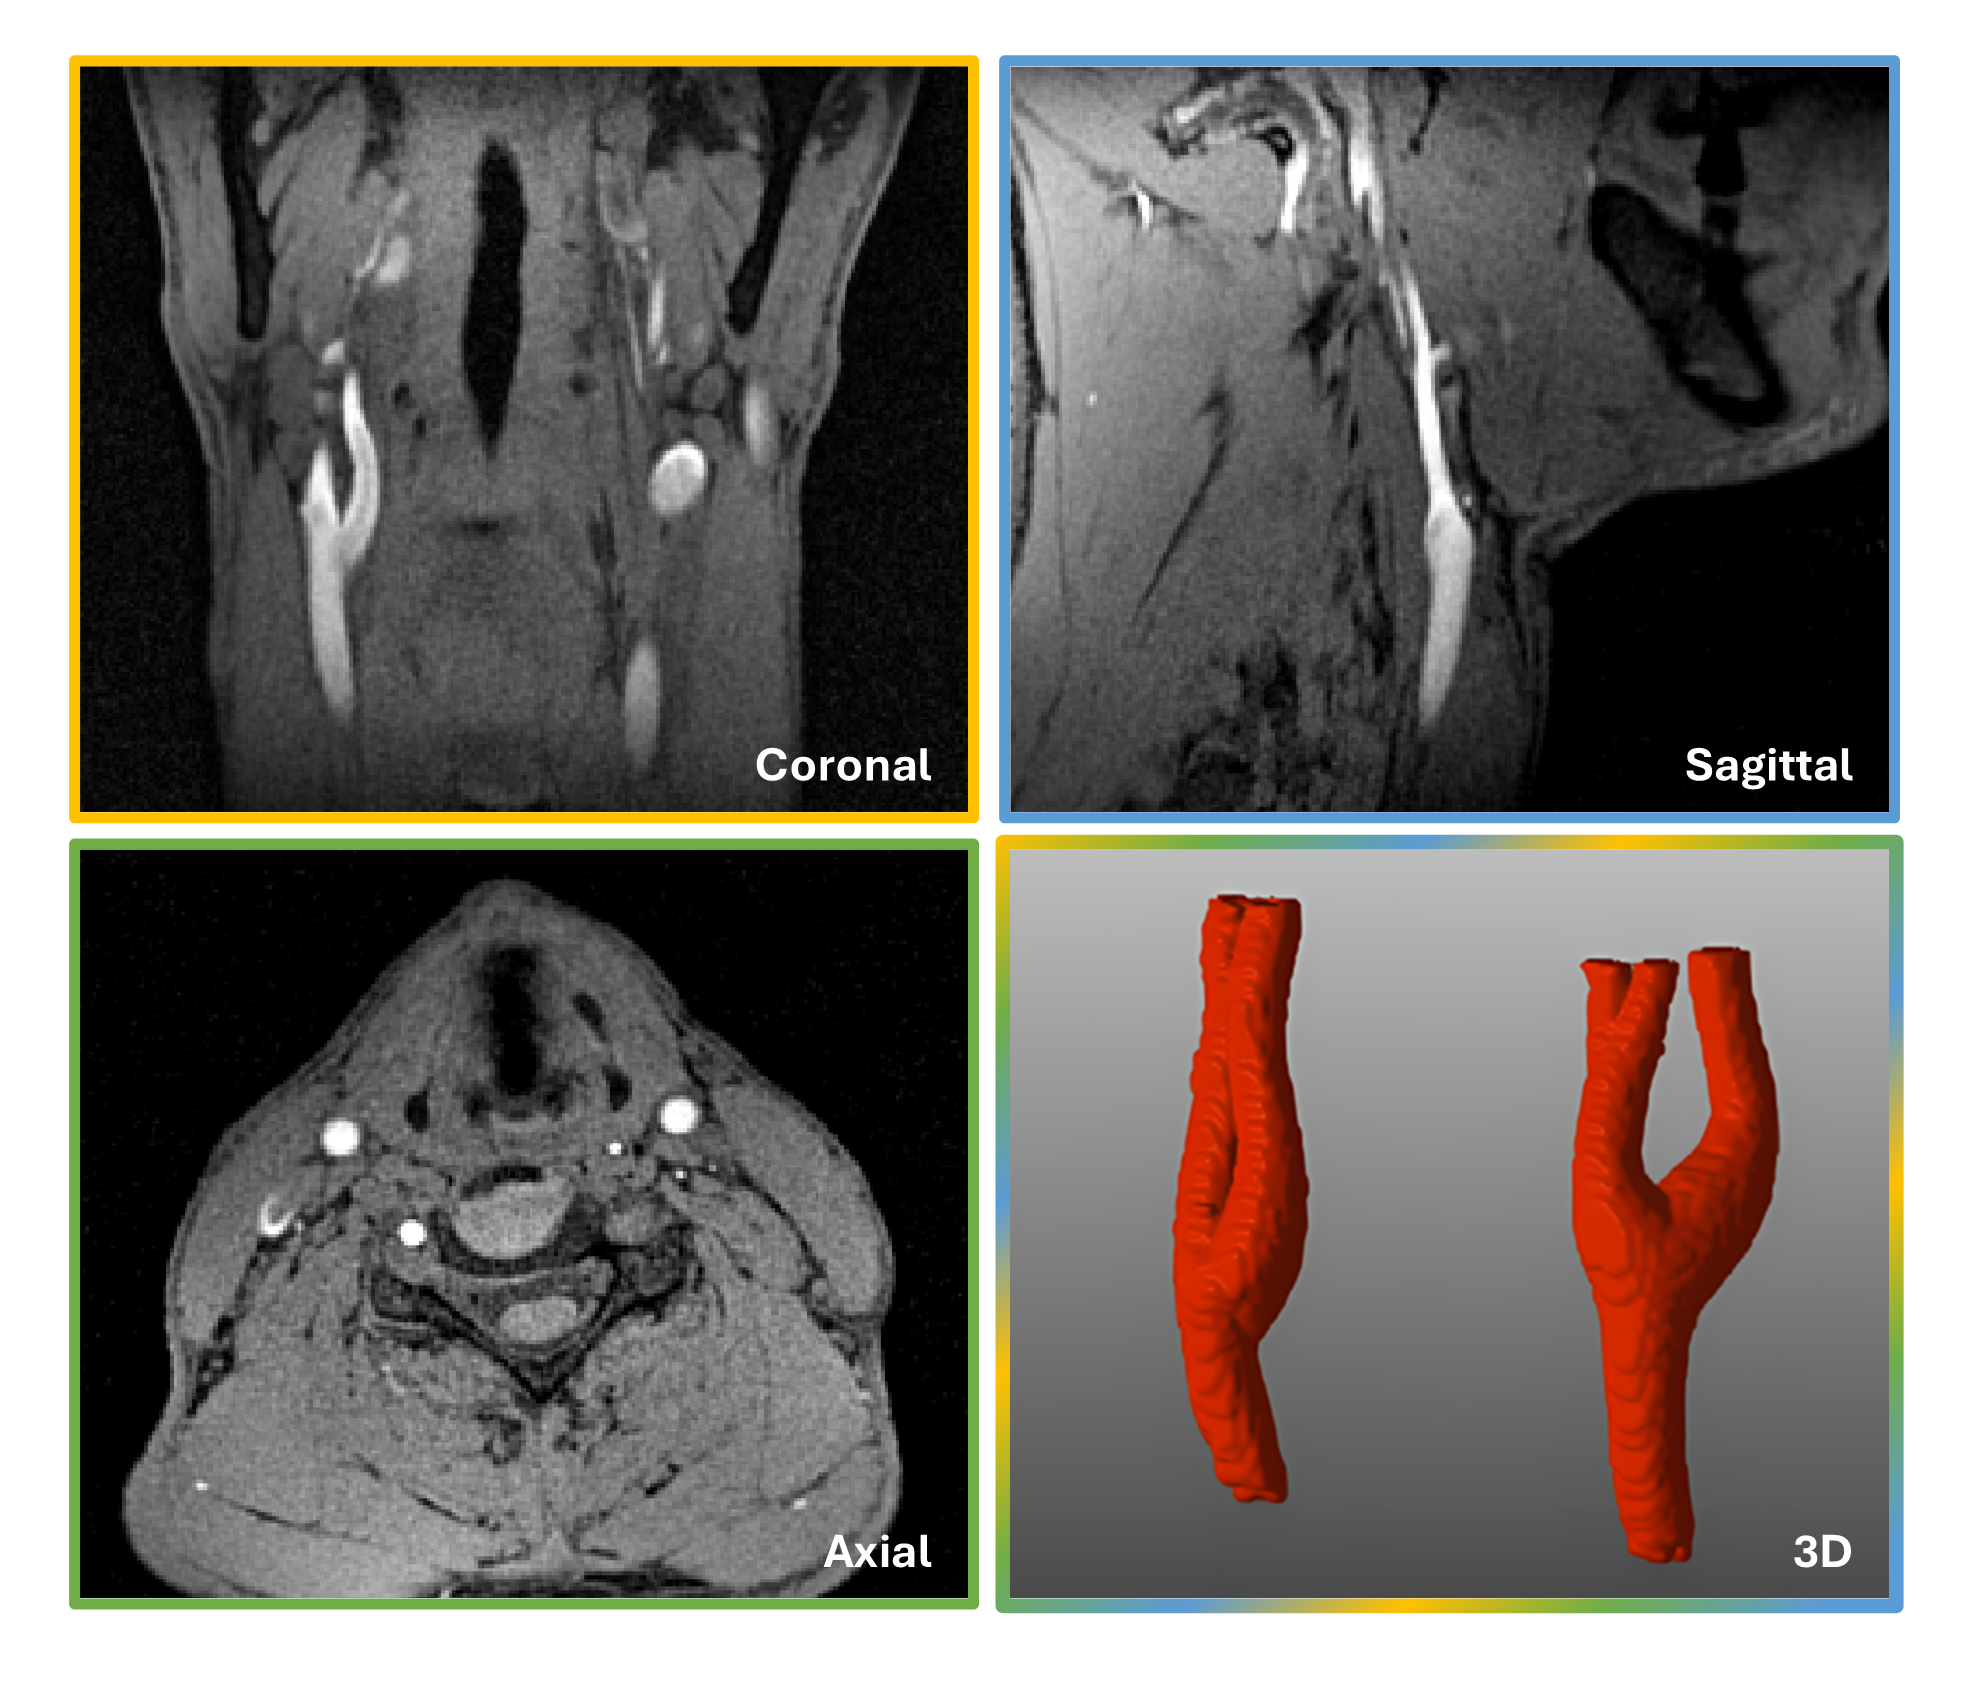

Figure 2. Three example orthogonal anatomical views of the neck and carotid arteries in the MRA in a junior participant together with a 3D rendering of the carotid arteries. While the arterial blood has a bright signal, the lipid signals are largely suppressed by the water excitation.

Figure 2. Three example orthogonal anatomical views of the neck and carotid arteries in the MRA in a junior participant together with a 3D rendering of the carotid arteries. While the arterial blood has a bright signal, the lipid signals are largely suppressed by the water excitation. Figure 3. Stiffness-related measurements for both modalities and cohorts in the common carotid arteries. (A) Stiffness index (β) measurements showed no statistical significance between modalities while there was an age-related increase of β when comparing the junior and senior cohorts (p_MRA = 0.002 and p_US = 0.005).(B) Local pulse wave velocity (PWV) values were significantly higher for the senior cohort in both modalities (p_MRA = 0.0005 and p_US = 0.003) while there were no statistical differences between MRA and US.